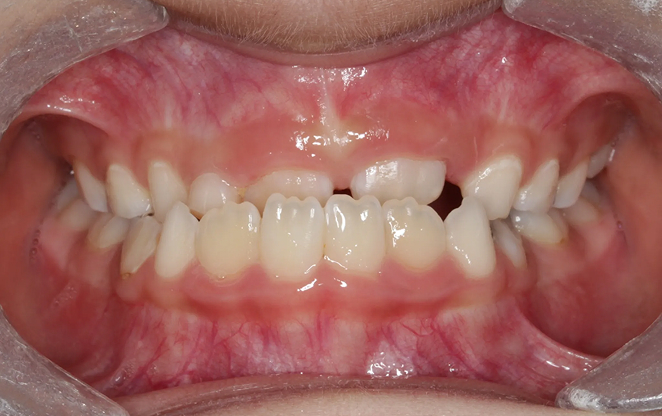

초등학생 1차 교정은 영구치가 나오기 전 혼합치열기에 시작하는

교정입니다. 이 중요한 시기에 치아가 제대로 자리 잡을 수 있도록,

아이의 밝은 미래를 위한 준비를 도와드릴게요.